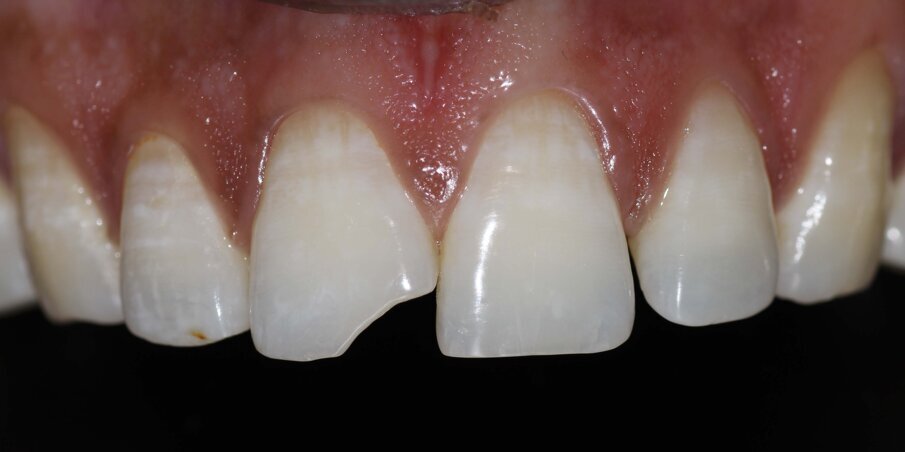

A 32-year-old man walks into our dental office with the chief complain of a broken front tooth. On examination, a Class IV fracture is seen involving the enamel and dentin of 11. The IOPA did not show any significant findings, and the tooth reacted positively to vitality testing.

Fig 2: Pre op Intraoral

Fig 11: Tight proximal contact achieved. Final intraoral picture after finishing and polishing